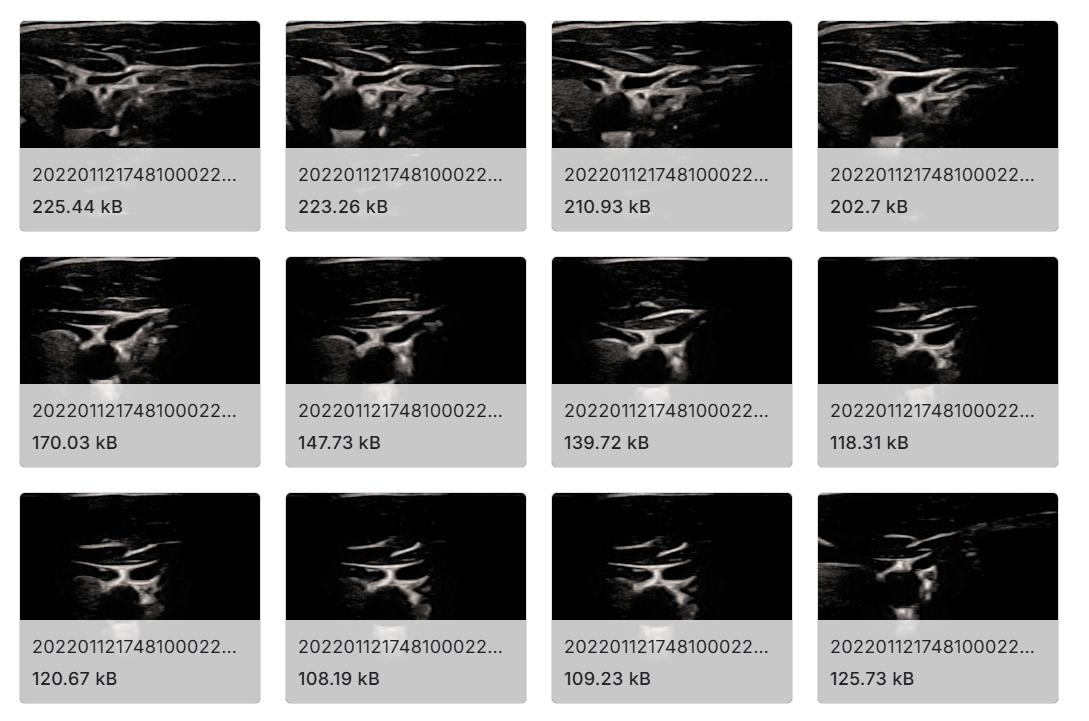

该数据集共包含 2200 张高质量超声图像,取自 11 个不同的主题,每个人的左侧和右侧至少检查一次。这些图像使用带有 L500-13s 线性探头的 Mindary UMT-3Plus 超声机获得。在研究组的 11 名参与者中,2 名使用血管模式进行检查,8 名使用颈动脉模式进行检查。图像的分辨率是 709 x 749 x 3(RGB),格式为 PNG。

- 超声图像 :从每个受试者拍摄 100 张超声图像,共 1100 张图像。